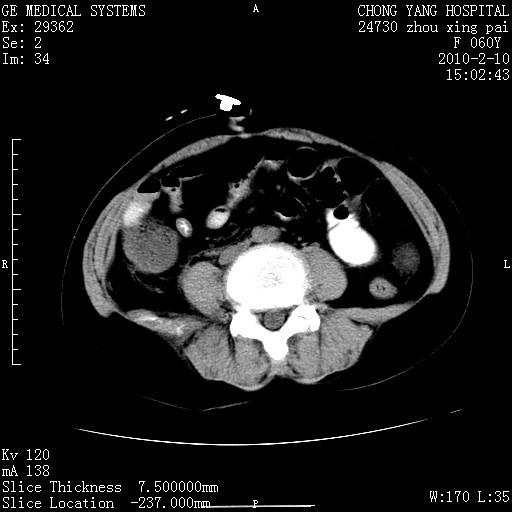

胆总管末端梗阻!结石?胰腺影增粗,以胰腺头部为著,胰周看见渗出影,双侧胸腔积液,(胸膜反应)考虑胰腺炎。

1)胆总管末端梗阻,不排除结石所致可能。2)胰腺炎。3)慢性胆囊炎可能。4)左侧输尿管上段扩张。5)少量腹水。6)双侧少量胸腔积液,伴两下肺部分肺萎陷。

1)胆囊炎。2)胆源性胰腺炎。3)右肾周筋膜增厚,肾旁前间隙积液。4)左侧输尿管上段扩张。5)少量腹水。6)双侧少量胸腔积液,伴两下肺部分肺膨胀不全。

1)胆总管末端梗阻。2)胰腺炎。3)慢性胆囊炎可能。4)左侧输尿管上段扩张。5)少量腹水。6)双侧少量胸腔积液,伴两下肺部分肺萎陷。